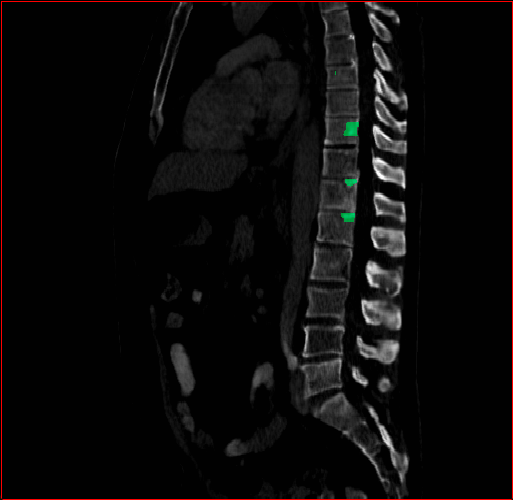

Figure 3 shows the generalizability of MAISI-v2 ControlNet for different body regions and voxel sizes. Figure 4 shows qualitative results for MAISI-v2 ControlNet on 5 types of tumors.

Figure 3: MAISI-v2 segmentation-guided results for small to large volume size and three different regions.

Lung Tumor

0.75×0.75×0.60.75\times 0.75\times 0.6

mm

512×512×512512\times 512\times 512

Figure 4: MAISI-v2 segmentation-guided results for five types of tumors. We show results for different voxel spacing and volume size to demonstrate the flexibility of MAISI-v2. Different Hounsfield Unit window is used to better show the contrast between tumor and normal tissues.